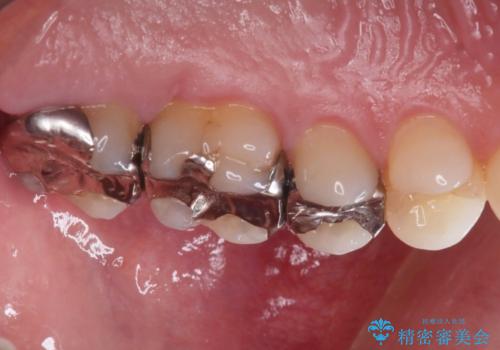

【メタルフリー】銀歯を綺麗な白い歯に

- 銀歯の入っている部分にフロスが引っかかるため、銀歯を適合の良い白いセラミックインレーにやりかえることを提案させていただきました。

一番奥の歯は銀歯に覆われている範囲が多いため、強度などを踏まえ被せ物にしました。

その他2本は詰め物です。